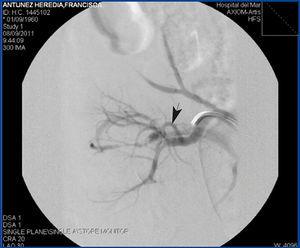

Se practicó cateterismo selectivo de arteria renal por vía femoral con catéter Vanschie. La angiografía puso de manifiesto una FAV en rama renal segmentaria de alto débito y de otras dos de menos entidad dependientes de esta, todas ellas a nivel del tercio medio del riñón (figura 1). Se procedió a cateterizar la rama renal afecta, liberando dos microcoils (Cook) de 0,5 cm para tratar la fístula de alto débito. Las dos fístulas restantes se trombosaron espontáneamente tras cateterizar la rama afecta con catéter multipropósito y de forma previa a una liberación adicional de microcoils.

Figura 1. Arteriografía renal selectiva que evidencia fístula arteriovenosa en rama renal segmentaria.